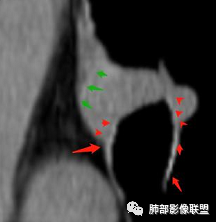

南边分析:针对本例,病灶跨气管壁内外生长,常规跨内外的有:恶性肿瘤为主,其次就是神经源性、平滑肌瘤;常规的思维:跨内外就要看结构的变化气管的优势在于软骨相对密度高,而且成C型

我们如何分析这个病例?冠状位:软骨密度稍高;病灶区软骨部分区域不连续,外围连续,提示病灶推移为主,不是破坏为主;如果破坏,应该这些软骨显示不清,移位不明显

病灶从软骨见推移开,跨内外,因此定在良性。恶性是侵犯,破坏为主,如果破坏,应该这些软骨显示不清,移位不明显,不是推移为主这例病变定在良性,我们就要考虑:1、软骨之间的平滑肌来源;2、神经源性

南边:

南边:高密度软骨在这两点上停了

南边:挤过去了,说明是从软骨间过去的

尘缘:@Shelia,部分是向前推,部分是向后推的。这个地方应该还有向后推的;肿物是从向前推与向后推这个间隙跨软骨的。

南边:需要用连续的窄窗观察。